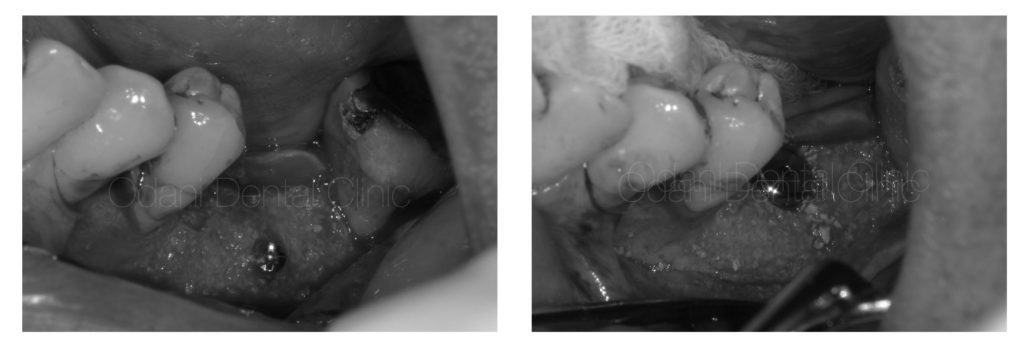

そして約半年待って骨が固まった状態で、インプラントを埋め込んでいきました。

インプラント埋入

骨が十分に形成されていたため、インプラント埋入手術は短時間で終えることができました。

歯肉移植を伴った頭出し手術